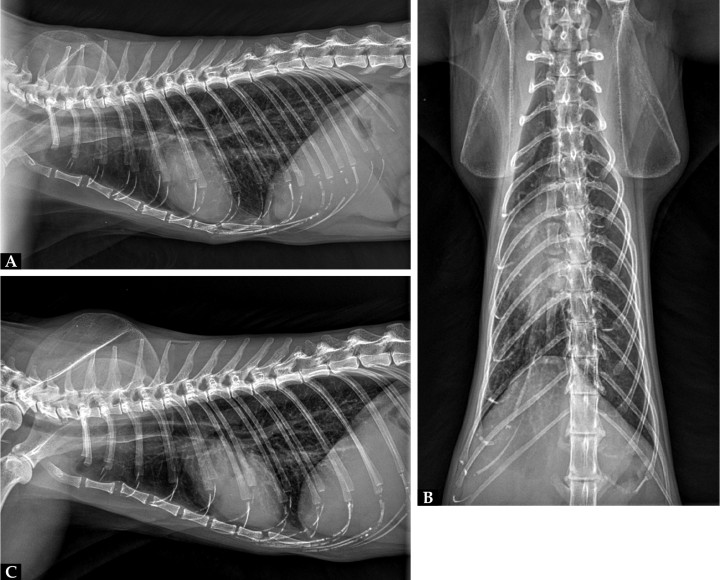

La ecografía abdominal no reveló alteraciones significativas, y los órganos y estructuras evaluados se encontraron dentro de la normalidad. Las radiografías torácicas en tres proyecciones no mostraron signos radiológicos significativos, mostrando una imagen del patrón pulmonar, mediastino y silueta cardiaca normales y sin evidencias claras de masas o efusión pericárdica (Fig. 2).

Figura 2

Imágenes radiográficas. (A) Proyección lateral derecha. (B) Proyección ventrodorsal. (C) Proyección lateral izquierda.